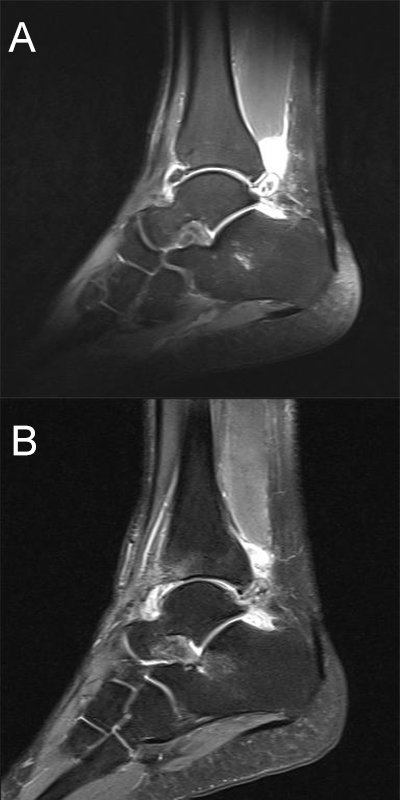

Die Magnetresonanztomographie (MRT) hat gezeigt, dass Knochenprellungen („bone bruises“), Knorpelschäden und andere Weichteil-Verletzungen erkannt werden 13 und mit arthroskopischen Befunden korrelieren 14.

Obwohl die MRT mittlerweile als Goldstandard für die Beurteilung von OCLs gilt sollte bedacht werden, dass aufgrund der hohen Sensitivität der Methode die Signalmuster im Sprunggelenk die Schwere der Knochenverletzung überschätzen können. Zudem wurde die gleiche diagnostische Genauigkeit für CT und MRT festgestellt 15.

Zur Vollansicht und zum Lesen der Bildbeschreibung bitte das Bild anklicken.